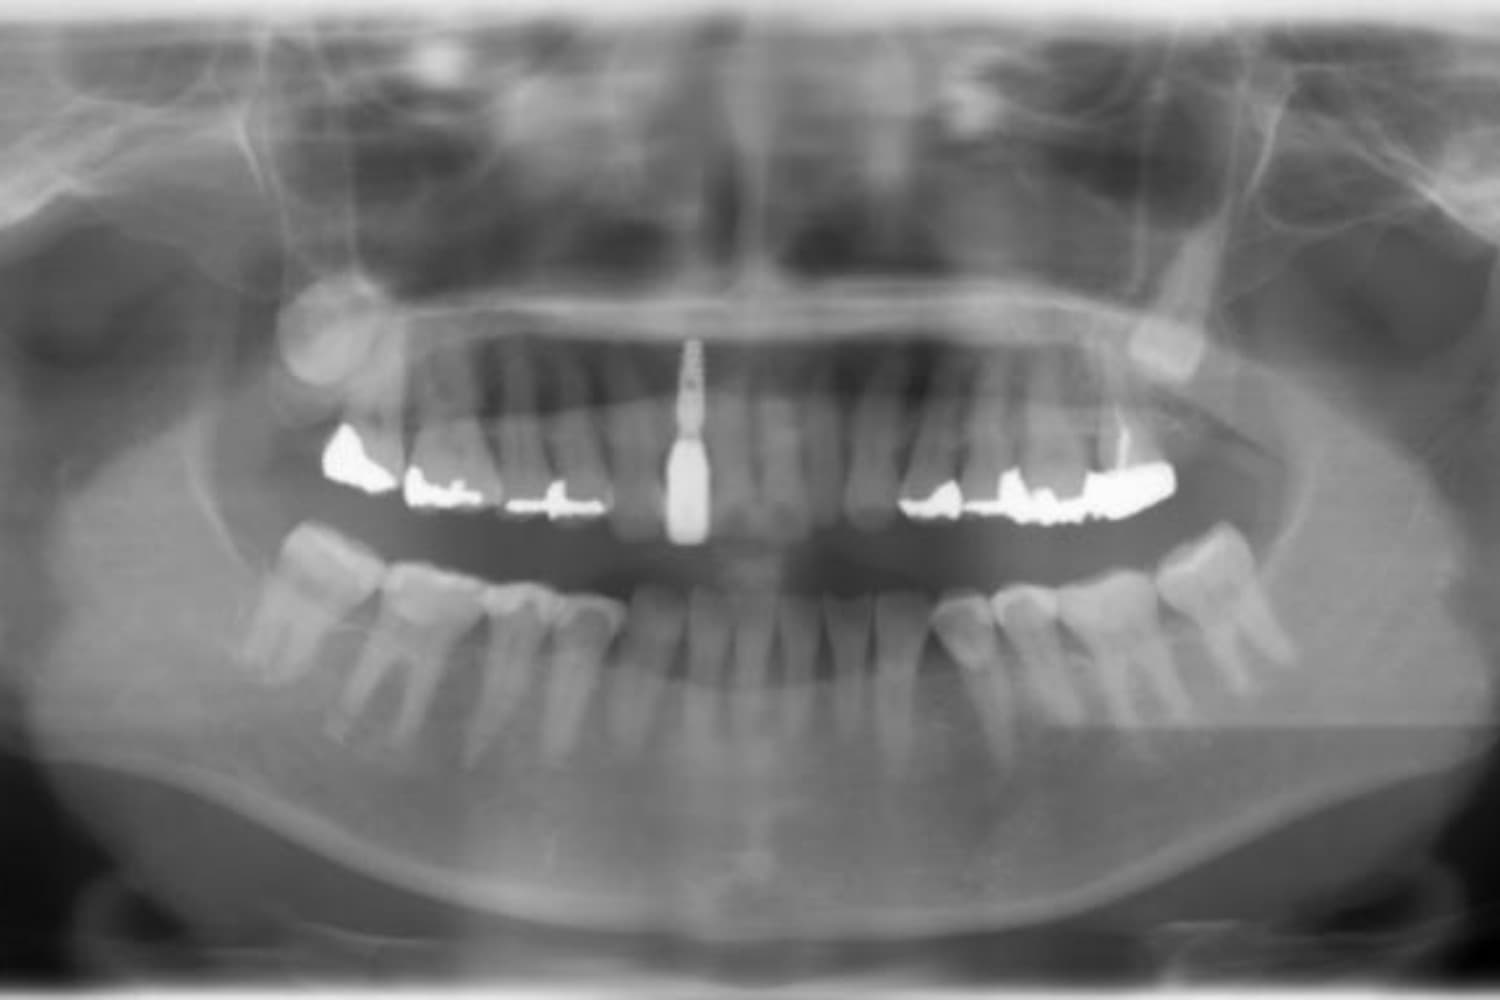

上顎前歯1本欠損症例(2)

After

歯の根の先に炎症が広がっていたため抜歯をおこないました。その後、土台となる骨を作る処置をおこなった後、インプラントを1本埋入しました。

年齢

70歳

性別

女性

主訴

歯肉の腫れ

治療期間

10ヵ月

費用

60万円